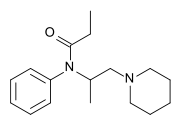

Ampromides

Structures

| Ampromides | ||||

| ||